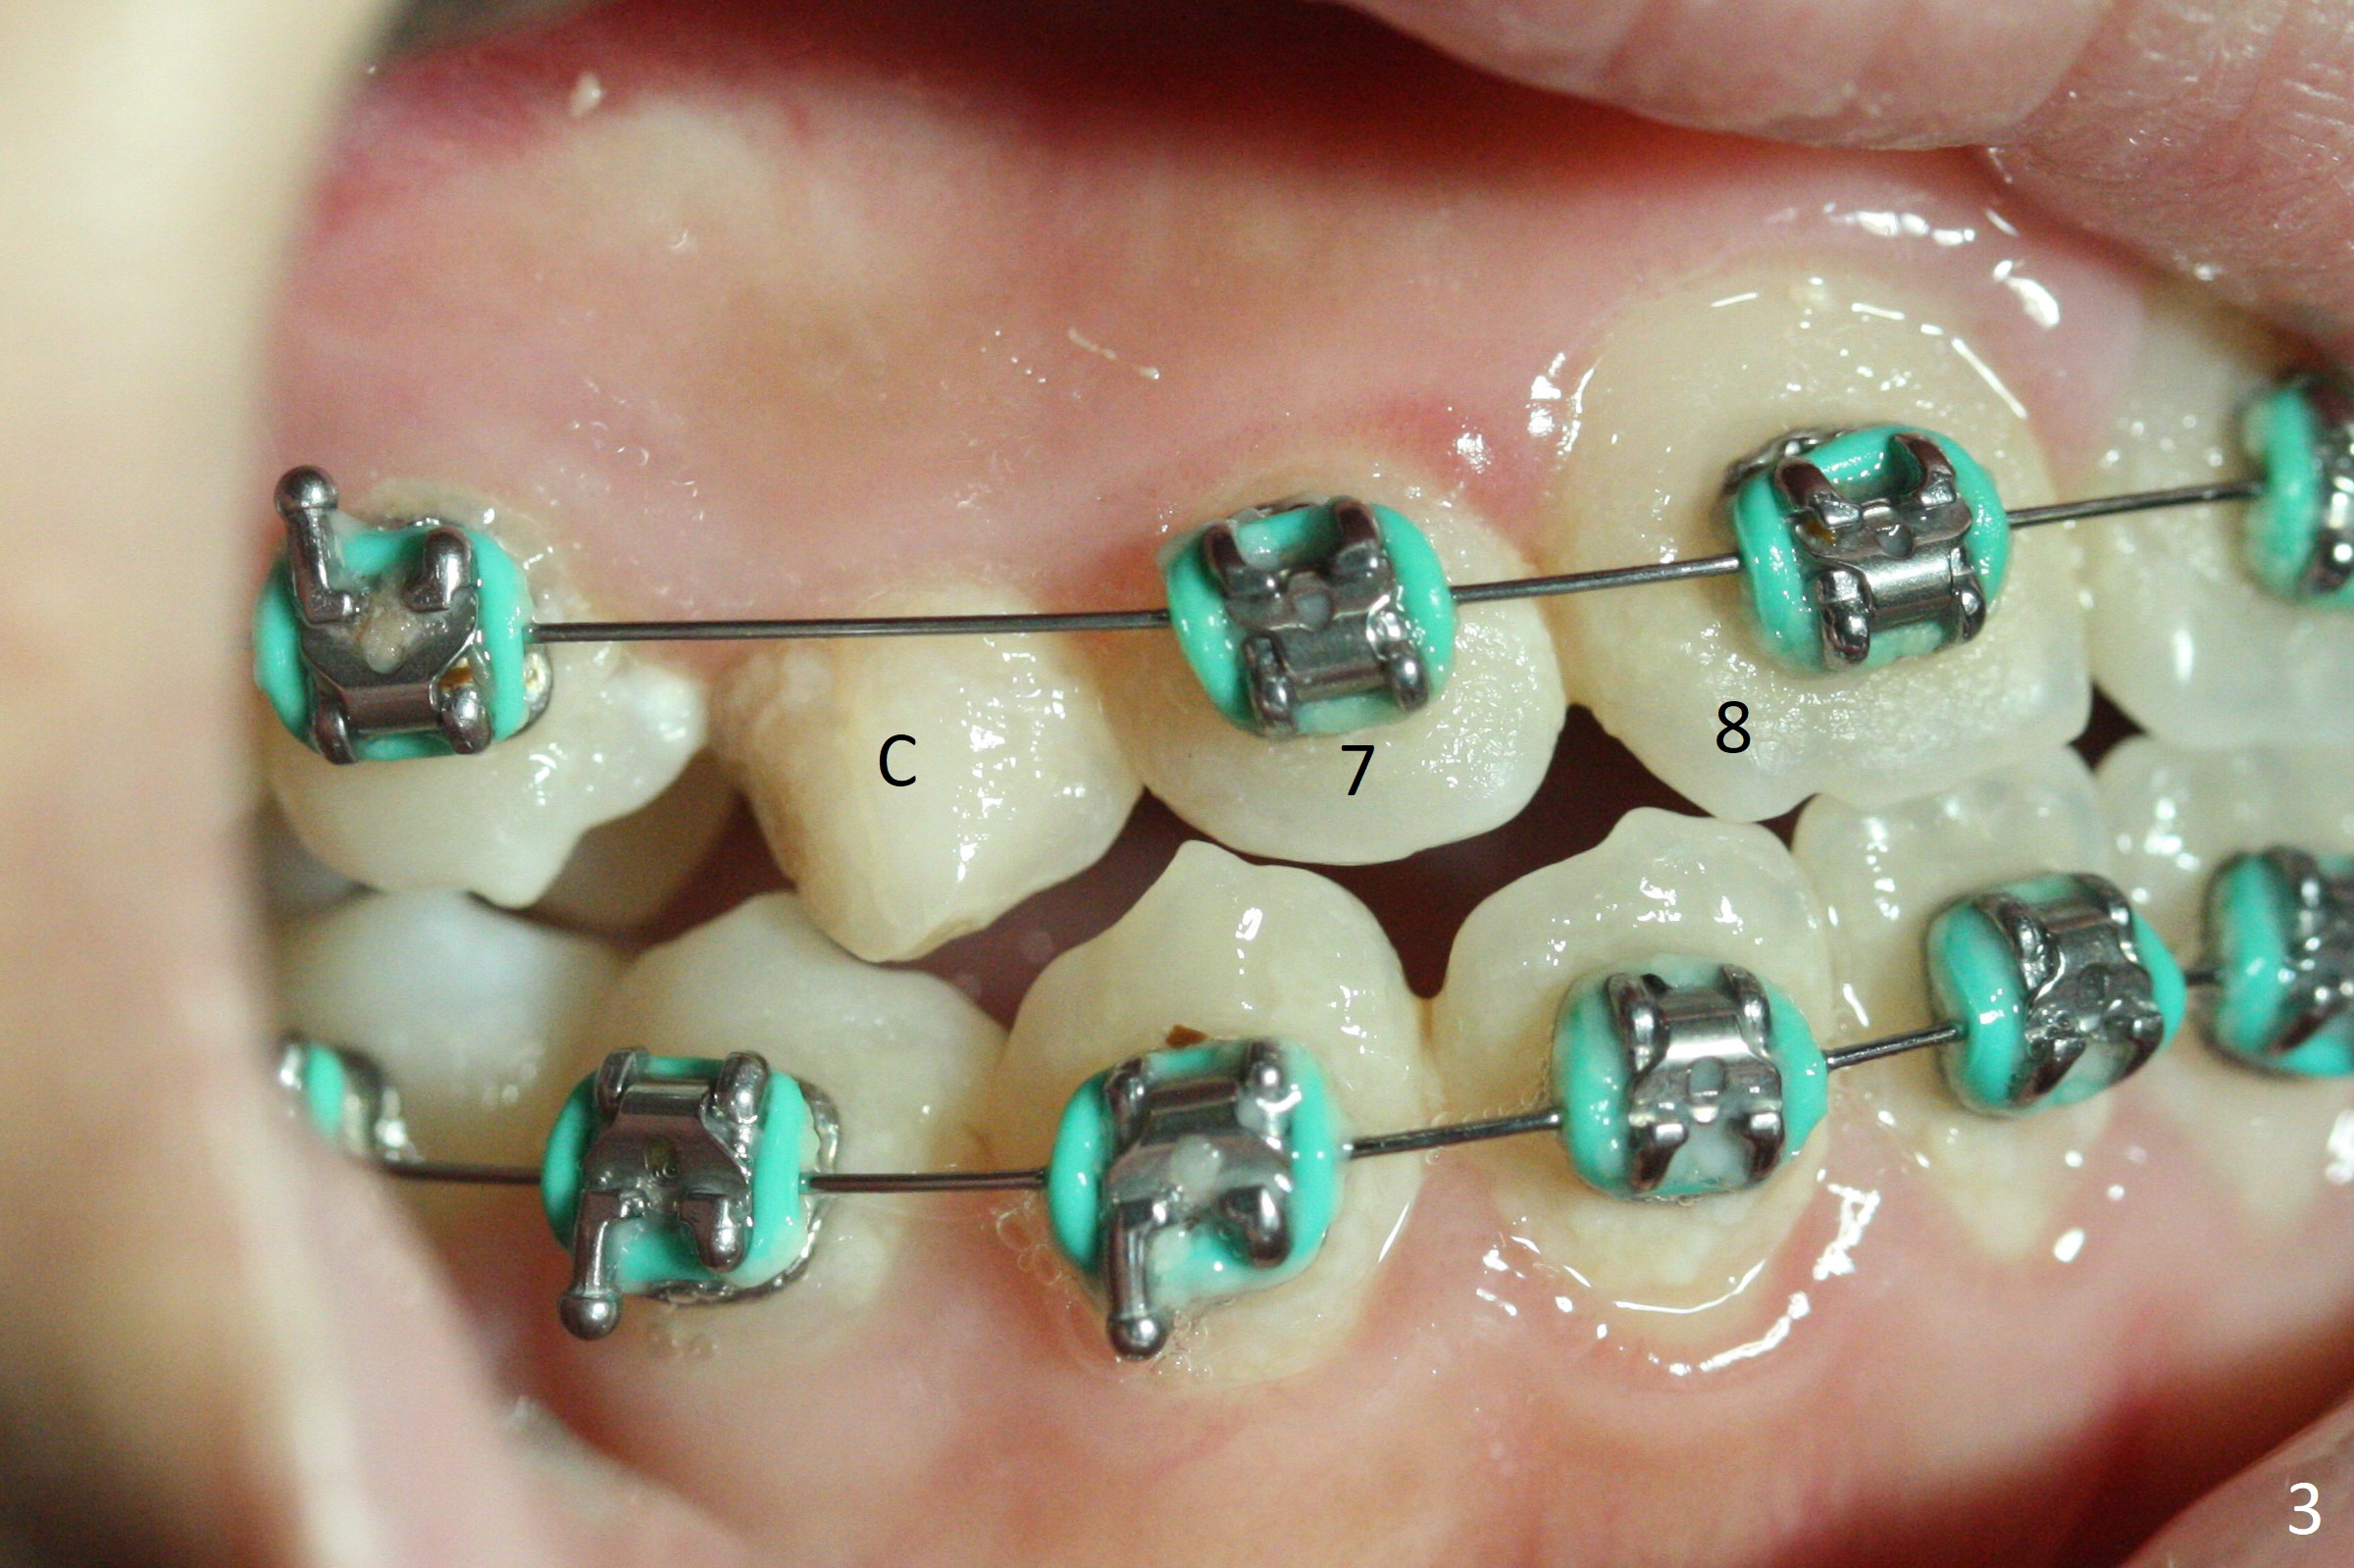

A 13-year-old woman has an impacted canine (Fig.1 (6)) and retained deciduous one (C). After initiation of orthodontics, she returns for surgical access to the impacted canine and placement of device to facilitate eruption (Fig.2,3). Incision is made buccal (Fig.4), but there is no tooth buccal (Fig.5). Extraction of the deciduous canine does not reveal the impacted one (Fig.6), but there is palatal elevation (*). Palatal access shows the impacted tooth (Fig.7) and allows placement of a retraction device (Fig.8). Careful clinical exam and CBCT are necessary diagnostic steps.